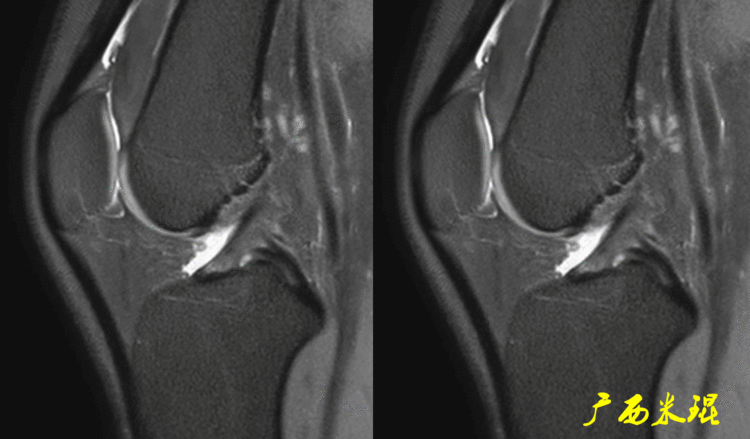

一、半月板损伤MR诊断的思路1、单纯就半月板改变诊断半月板损伤半月板信号(3级信号)及形态的异常是诊断半月板损伤最为直接的征象,当我们在阅片当中发现这些征象,一般情况下都能够确诊半月板损伤,下面这张MR,我们发现外侧半月板后角出现3级信号,所以能够确定其半月板损伤。

2、从发病机制诊断半月板损伤并不是每个病人都能够这么清晰的显示半月板的信号改变,同样这张MR,我们发现患者出现明显的对吻征,対吻征是诊断ACL损伤的重要体征,说明病人受伤的同时膝关节扭转严重,甚至出现轴移,这种情况下(损伤/发病机制)外侧半月板后根极其容易受伤,我们再认真的阅看其他截面,就很容易找到半月板损伤的佐证。